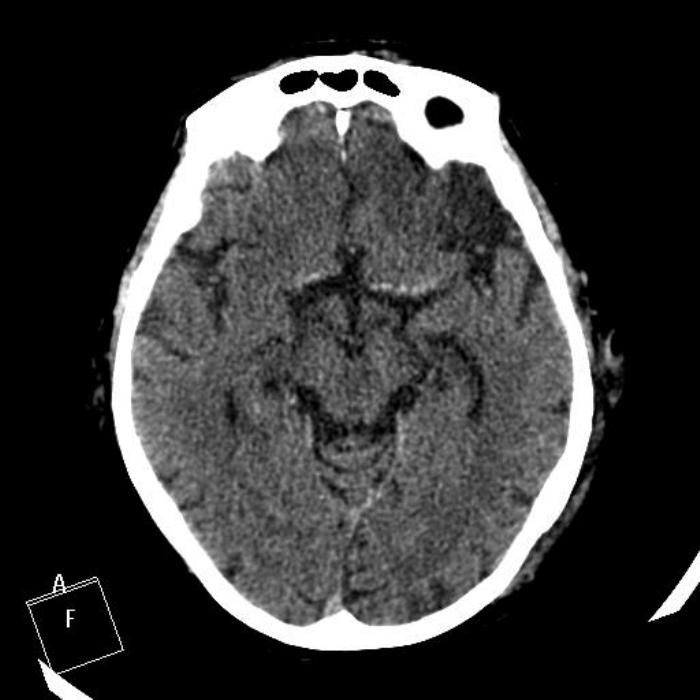

Женщине 70 лет. КТ примерно через 1,5 суток после начала заболевания (нашли соседи, а сколько пролежала - неизвестно точно). Как расценить изменения в левой лобной доле? А справа? Невролог считает, что термин "ишемический инфаркт с геморрагической трансформацией по типу гематомы" подходит для осложненного инсульта, т.е. геморрагия вторична, развивается позже как осложнение. Как правильно писать, есть ли термин "смешанный" инфаркт на КТ?

Я описала как ишемический инфаркт в бассейне правой СМА с геморрагической трансформацией по типу малой внутримозговой гематомы; подострый?/последствия? ишемического инфаркта лобной доли слева. Но сомневаюсь в правильности и трактовки левосторонних изменений, и в правильности КТ-заключения. Помогите, пожалуйста, разобраться!

Справа подострый /начало лизиса гематомы/ ишемический инфаркт с геморрагическим компонентом=трансформацией. Слева более старый ишемический инфаркт, ≈2-3 недели давность.

1. "Смешанный" инсульт - это жаргон, в МКБ-10 его нет. Поэтому не должно быть и в заключениях. 2. ==термин "ишемический инфаркт с геморрагической трансформацией по типу гематомы"=== А почему по типу гематомы, а не пропитывания. Лучше остановиться на "ишемический инфаркт с геморрагической трансформацией" 3. ==Невролог считает, что термин "ишемический инфаркт с геморрагической трансформацией" подходит для осложненного инсульта, т.е. геморрагия вторична, развивается позже как осложнение.=== Именно так и есть.

Смешанный инсульт не пишите. Ишемический инфаркт с геморрагическим пропитыванием. Причиа геморрагического пропитывания всем понятна, наверно. Именно пропитывание, о гематоме тут речь не идет.